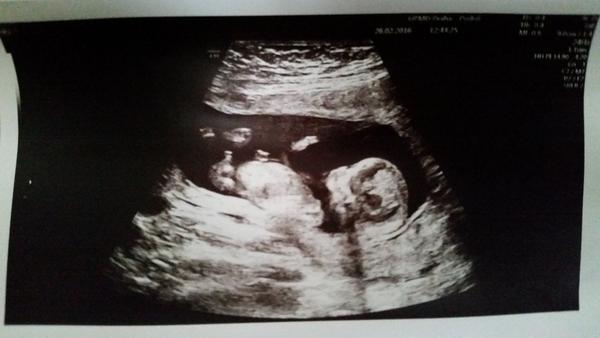

Je to holčička nebo chlapeček? Foto ultrazvuku

Obe fotky jsou podle me z boju. Na te prvni je i videt mereni doktora od hlavicky vlevo po zadecek vpravo. Ma tam i napsano crl, coz je to meteni. A to,co muze vypadat jako pindik,je ruka 🙂 zvetsi si fotku a tam to mereni crl od doktora uvidis

Ten vyvoj je dobre vidiet, zaujimave a vela vysvetli. Prave podla toho to vyzera a tiez su to teda fotky z profilu sa mi zda, ze ta moja horna foto kde sa meria crl prave ukazuje vybezok smerujuci dohora.. ale hned pod tym mi pride akoby kavove zrniecko ;). No asi vidim vsetko mozne. Mam doma uz dvoch chlapcov a teraz cakame jednovajky takze ak chalani tak bude veselo 🙂

@kmonk to mi prave prijde kolme,takze bych spis tipla holku. Ale moc drzim palce🙂 koukni na muj komplet deti 🙂))